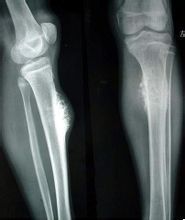

是最常見的骨惡性腫瘤,為一結締組織性肉瘤,其發展過程中可形成大量腫瘤性骨樣組織及骨組織。根據其新生骨的存在與否或多少而有溶骨性和成骨性的區別。病變常見於四肢長骨(脛骨上端或股骨下端)。10~25歲占發病者的大多數。

皮質旁骨肉瘤

特徵是發生於骨的表面,與骨膜及皮質旁結締組織有密切關係。其惡性程度較骨肉瘤為低,預後亦佳。好發於股骨下端,脛骨及肱骨次之。發病年齡以30歲左右為多見,病程發展緩慢,症狀輕微。軟骨瘤